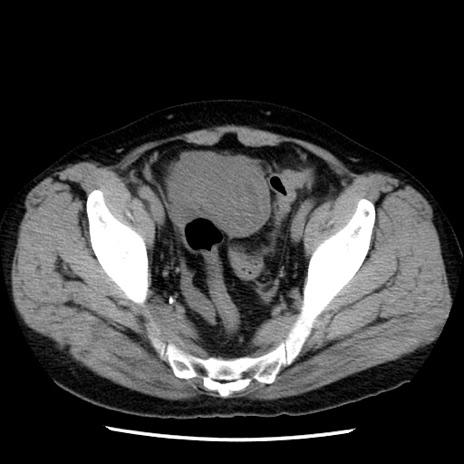

症例29(横断像)

【症例】40歳代男性

【現病歴】2日前から胃痛あり。徐々に周期的な激痛に変化した。本日になっても激痛があるため受診。

【身体所見】意識清明、BT 38-39℃台あり、腹部:膨満、やや硬、右下腹部に圧痛あり。

【データ】WBC 8500、CRP 23.26